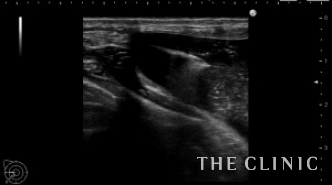

本日は4年前に他院でヒアルロン酸豊胸を行った後にしこりになった方を紹介します。

エコーでは大きなしこり以外にも小さなしこりを多数認めました。

一つ一つエコー下にヒアルロニダーゼで溶解して吸引除去します。

ヒアルロン酸注入によるしこりのエコー診断カルテ